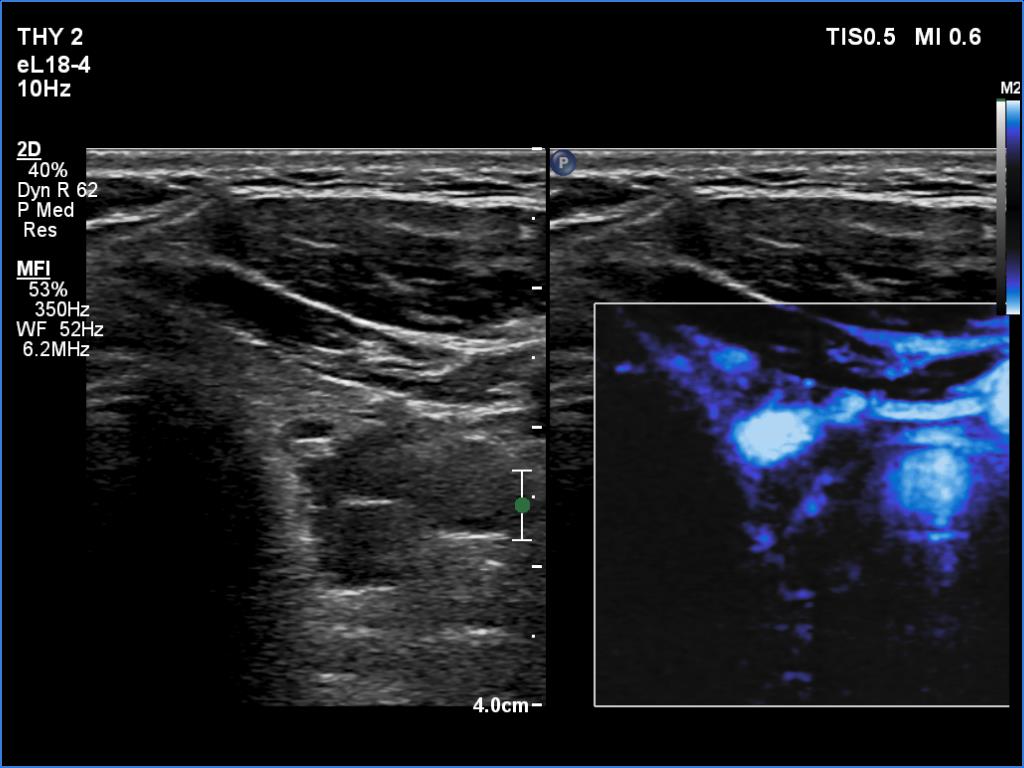

Right lobe, longitudinal scan

Left lobe, transverse scan, microflow imaging. There is a large vessel in the central part of the adenoma.